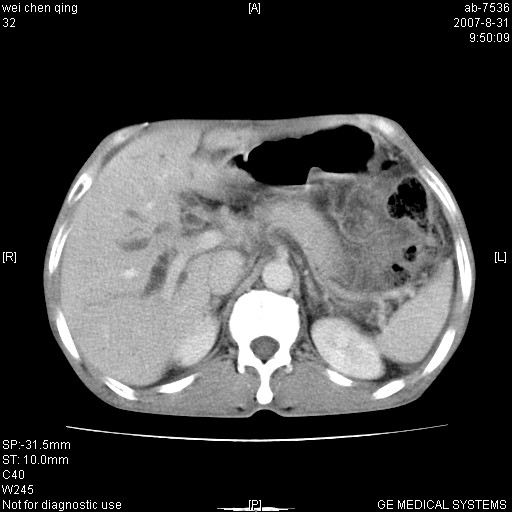

以下是引用zyyzzy在2007-8-31 14:34:00的发言:[br]该病人肝内胆管扩张,胆囊及胆总管未见明显扩张。在倒数第9层图像上可看到左右肝管结合部(肝总管)有软组织影,此处应薄层扫描。考虑肝总管占位(ca)、腹水。[br]